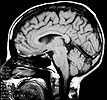

Cerebro

Vista Medial

Resonancia Magnetica

Encefálica